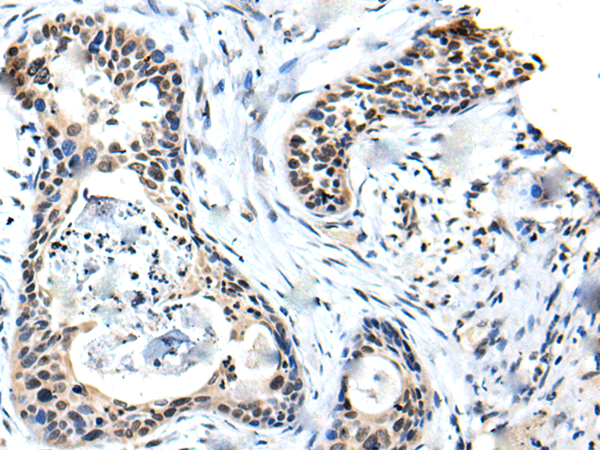

Product Image

The image is immunohistochemistry of paraffin-embedded Human cervical cancer tissue using (SOX4 Antibody) at dilution 1/20. (Original magnification: ×200)